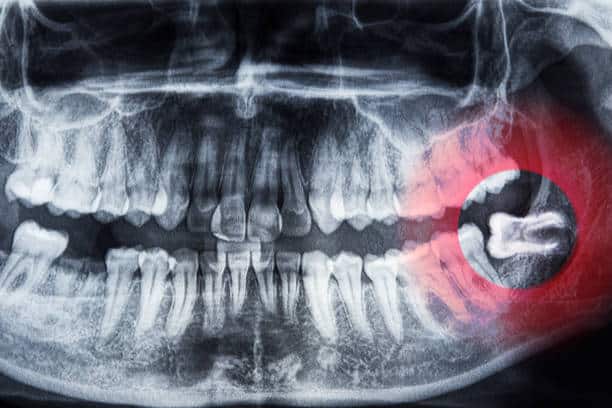

- Impaction: The tooth stays partly or completely under the gum.

In many situations, your general dentist may recommend early assessment or preventative removal, especially if X-rays show that the teeth are impacted or likely to cause issues later.

Your dentist will assess whether early removal is appropriate based on clinical examination and X-rays.

However, only a dental examination and X-ray can confirm this. Proactive evaluation helps prevent unexpected pain and complications later on.